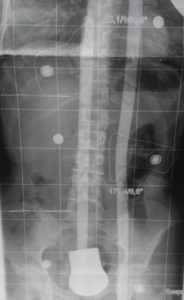

Durch jahrzehntelanger Erfahrung in der Behandlung von Wirbelsäulen können wir die Herstellung von fixierenden und stabilisierenden sowie wachstumslenkenden Rumpforthesen nach modernsten Kriterien gewährleisten.

Rumpforthesen werden eingesetzt, um die Wirbelsäule zu fixieren, zu korrigieren (Redression), aufzurichten (Reklination), zu entdrehen (Derotation) oder zu strecken (Extension). Unterschieden werden passive und aktive Rumpforthesen. Die passiven Rumpforthesen, auch Stützkorsetts genannt, werden zur Entlastung instabiler Wirbelsäulen eingesetzt, u.a. mit dem Ziel der Schmerzlinderung. Aktive Rumpforthesen sollen Fehlstellungen der Wirbelsäule korrigieren, wie sie bspw. als Folge von Erkrankungen wie Skoliose, Kyphose, Morbus Scheuermann, Hyperlordose und Osteoporose auftreten. Rumpforthesen werden bei Kindern und Jugendlichen eingesetzt, um das Wachstum zu lenken und Fehlstellungen zu korrigieren.